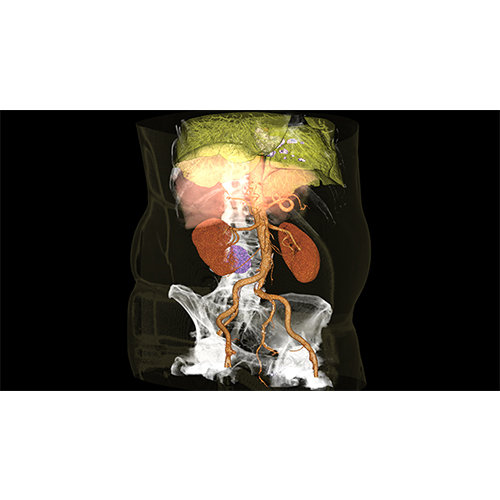

High-quality and fast 3D reconstruction and 3D rendering

Performs 3D reconstruction and volume rendering.

Instant and interactive surface extraction and export to STL and PLY formats.